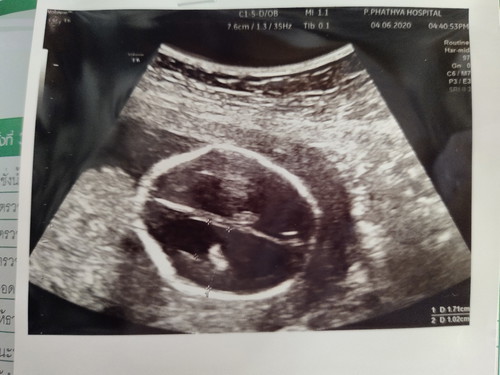

ลูกในครรภ์มีน้ำในสมองเยอะ

ตั้งครรภ์18W6Dไปหาหมอตามนัดหมอซาวและเจาะน้ำคร่ำ หมอซาวแล้วบอกว่าน้องเหมือนมีน้ำในสมองเยอะแต่ต้องรอผลเจาะน้ำคร่ำ3อาทิตย์แต่ตอนนี้เป็นกังวลว่าน้ำในสมองลูกจะหายไปไหม